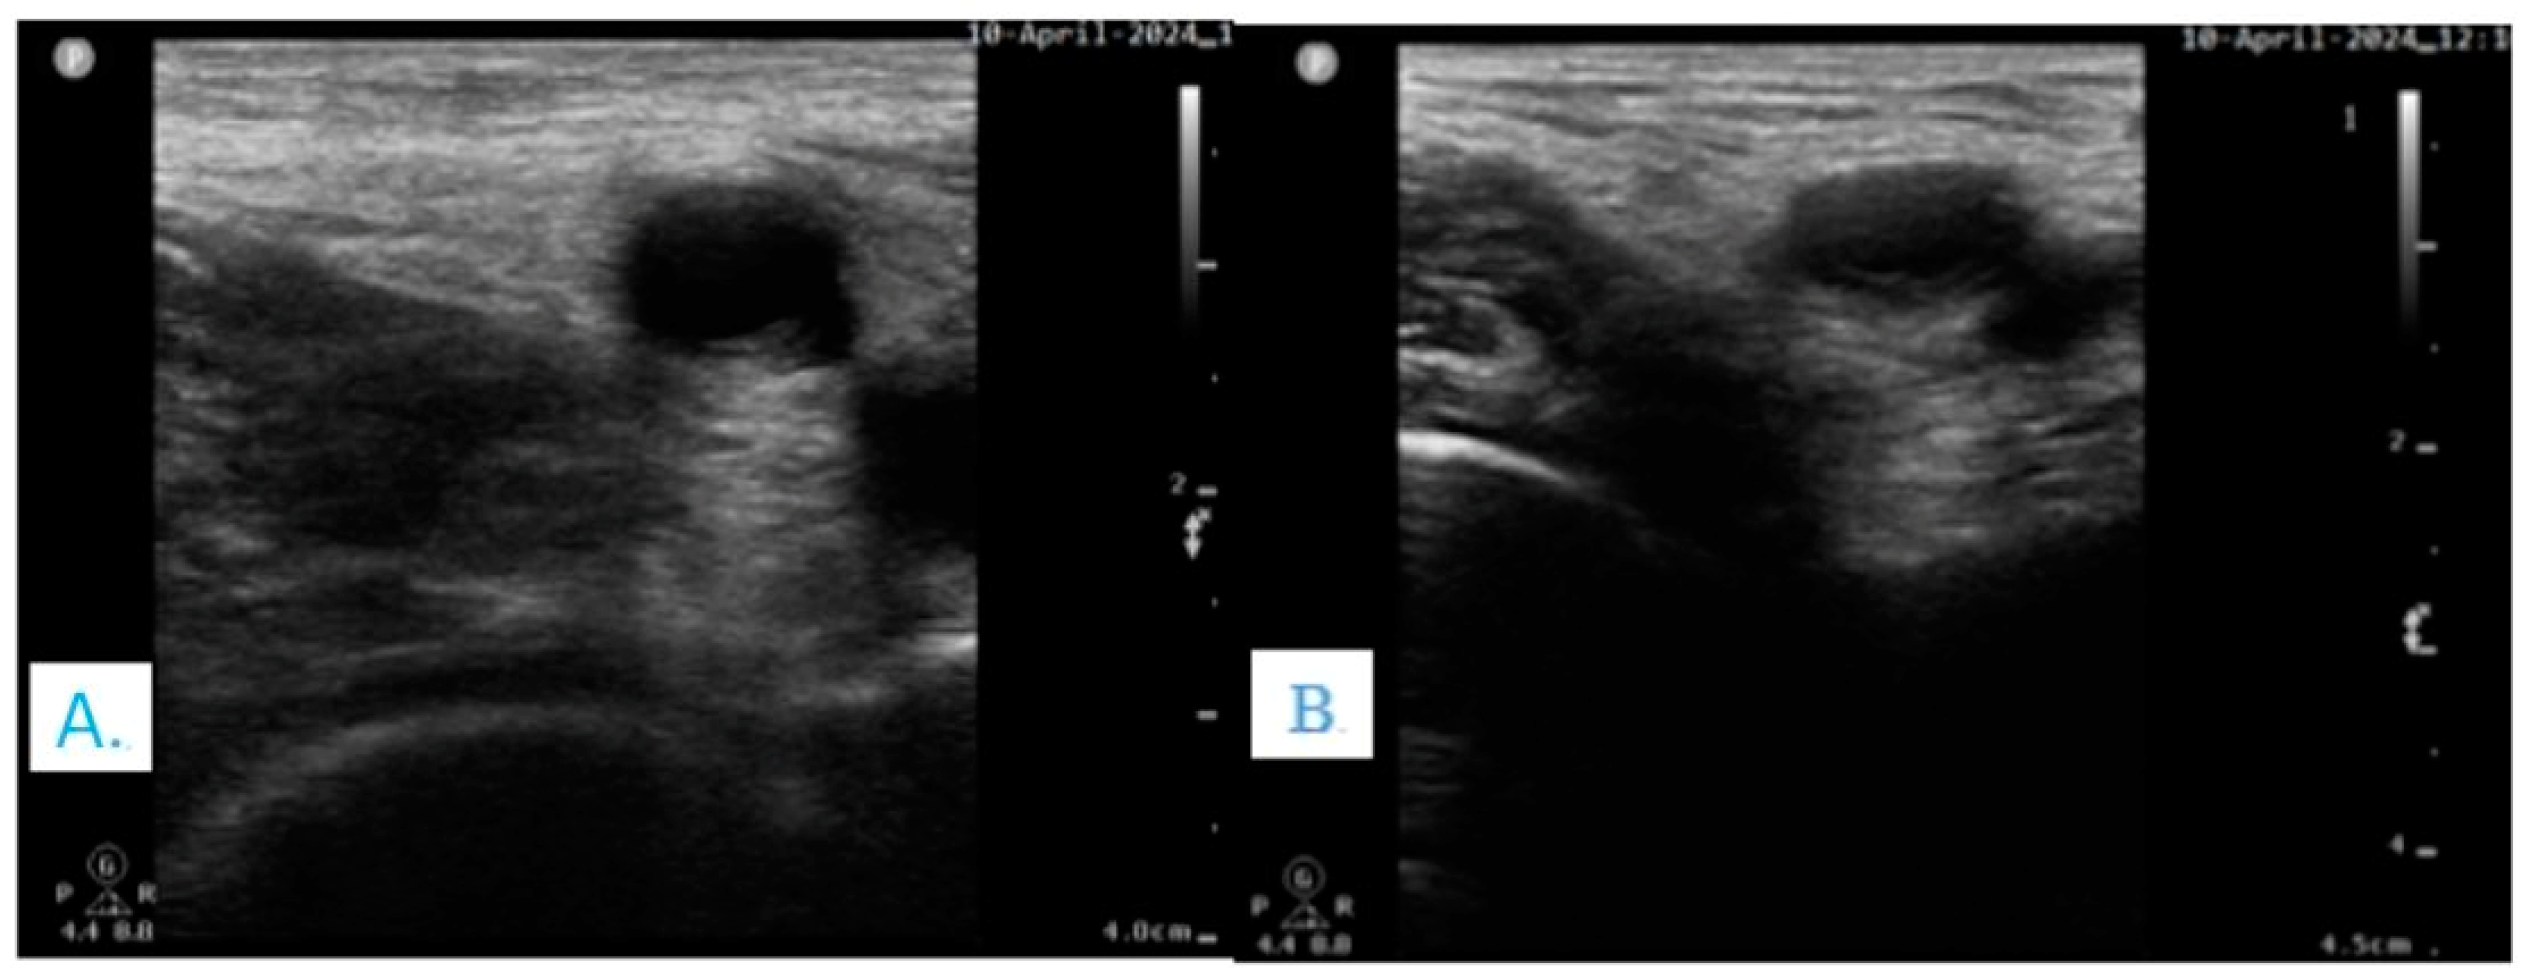

- Ketelaars, R.; Stollman, J.T.; van Eeten, E.; Eikendal, T.; Bruhn, J.; van Geffen, G.-J. Emergency physician-performed ultrasound-guided nerve blocks in proximal femoral fractures provide safe and effective pain relief: A prospective observational study in The Netherlands. Int. J. Emerg. Med. 2018, 11, 12. [Google Scholar] [CrossRef] [PubMed]

- Chen, L.; Shen, Y.; Liu, S.; Cao, Y.; Zhu, Z. Ultrasound-guided supra-inguinal fascia Iliaca compartment block for older adults admitted to the emergency department with hip fracture: A randomized controlled, double-blind clinical trial. BMC Geriatr. 2021, 21, 669. [Google Scholar] [CrossRef] [PubMed]